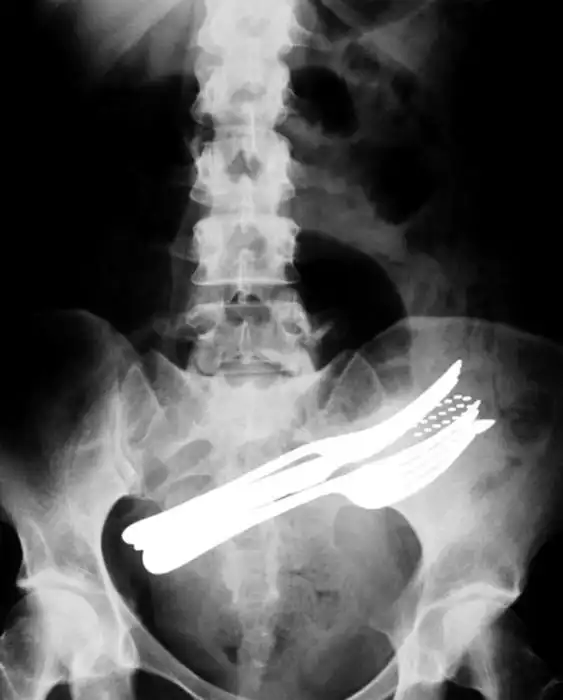

с оторванным пальцем уже не впечатляет, дурных детишек с такими травматическими ампутациями пальцев на работе насмотрелся и назашивался. Часть снимков с фатальными травмами. А с последней не понял. Ну тень средостения, ну загазованная толстая кишка, ничего патологического по костной системе не увидел, только в 10м межреберье слева хрень какая-то сеточкой.

на последнем, по моему бутылка

о теперь пригляделся увидел)